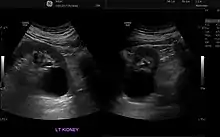

Ecografía renal

Se utiliza para obtener imágenes de los riñones, los uréteres y la vejiga. Se realiza este examen cuando los médicos sospechan de alguna problema renal y este les permite identificar:

- el tamaño de los riñones

- lesiones

- anomalías presentes desde el nacimiento

- obstrucciones o piedras en los riñones

- complicaciones por infección en el tracto urinario

- quistes o tumores[19]